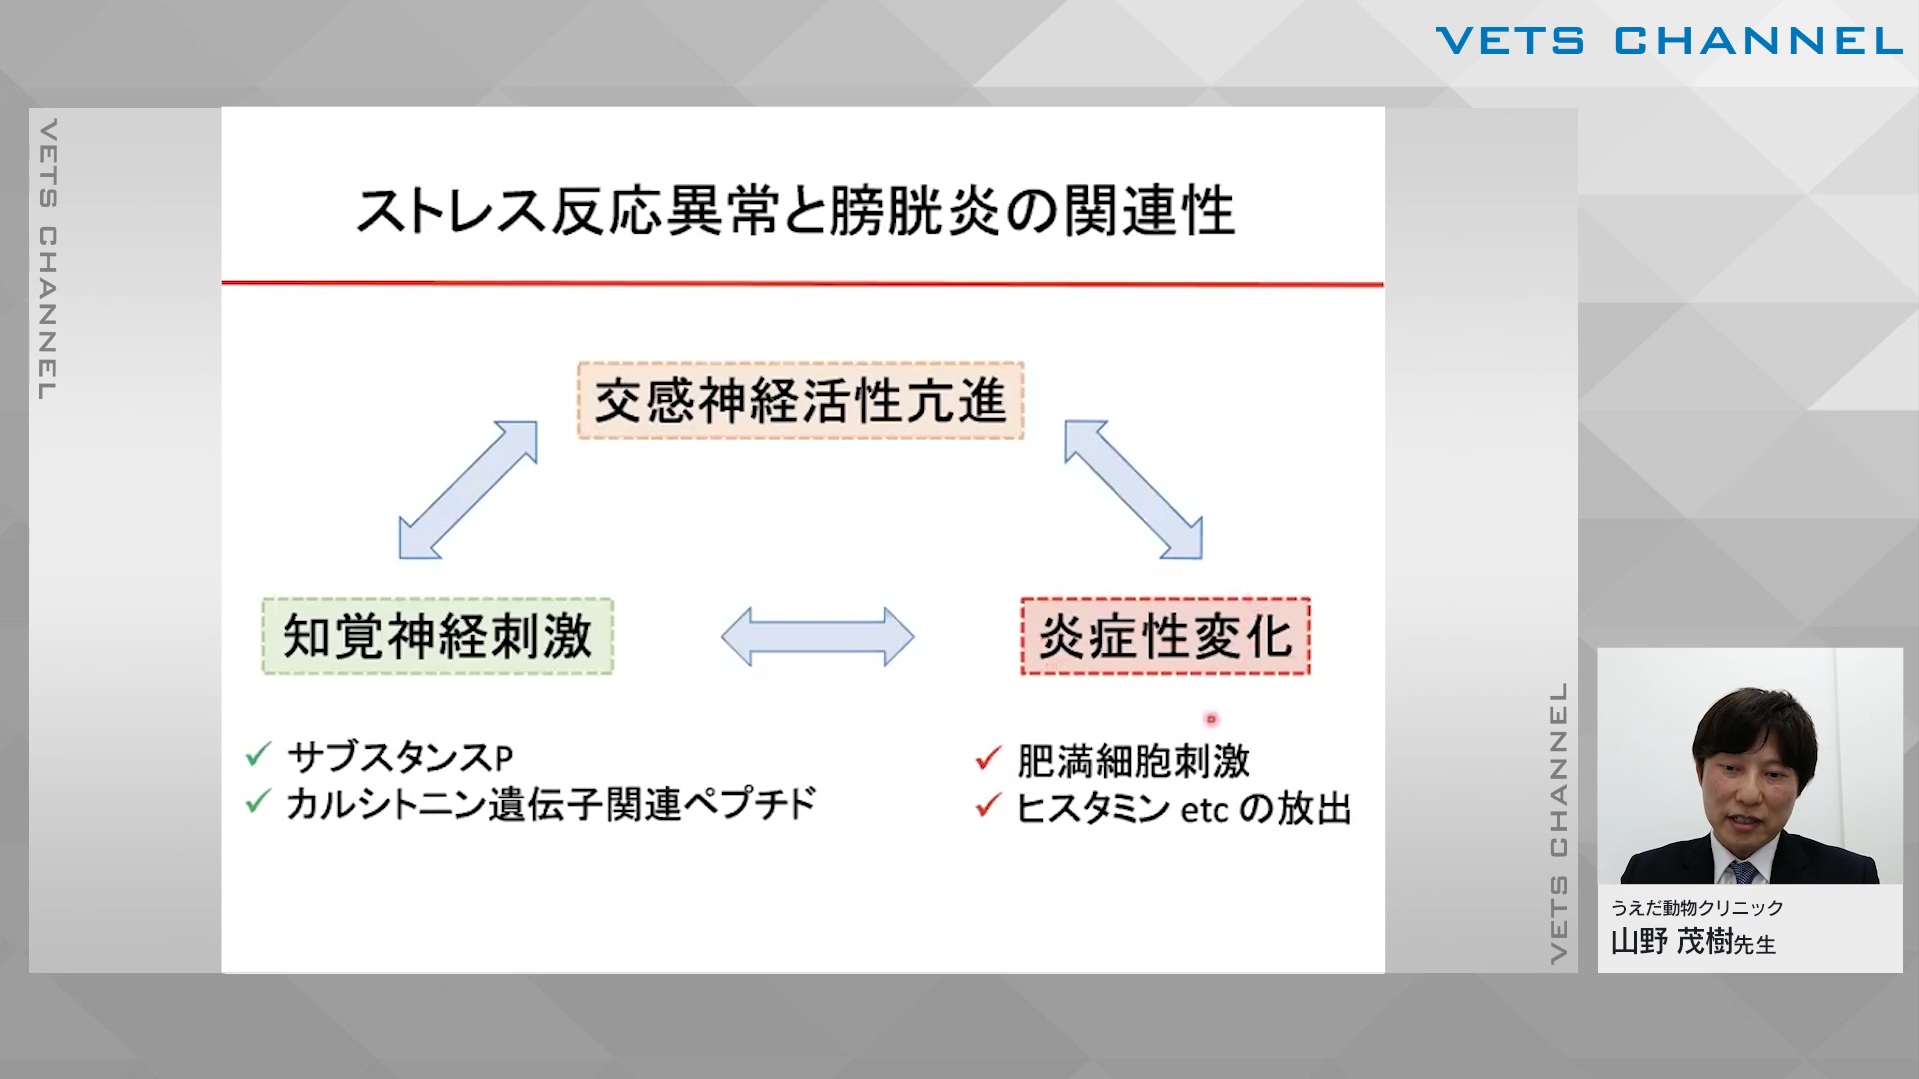

“猫ならでは”を知る 特徴的な疾患の診断と治療 第4回:腎泌尿器

- セミナー

- 内科全般

- 腎・泌尿器科

- 猫

山野 茂樹先生 (うえだ動物クリニック)

103分

2025/09/19